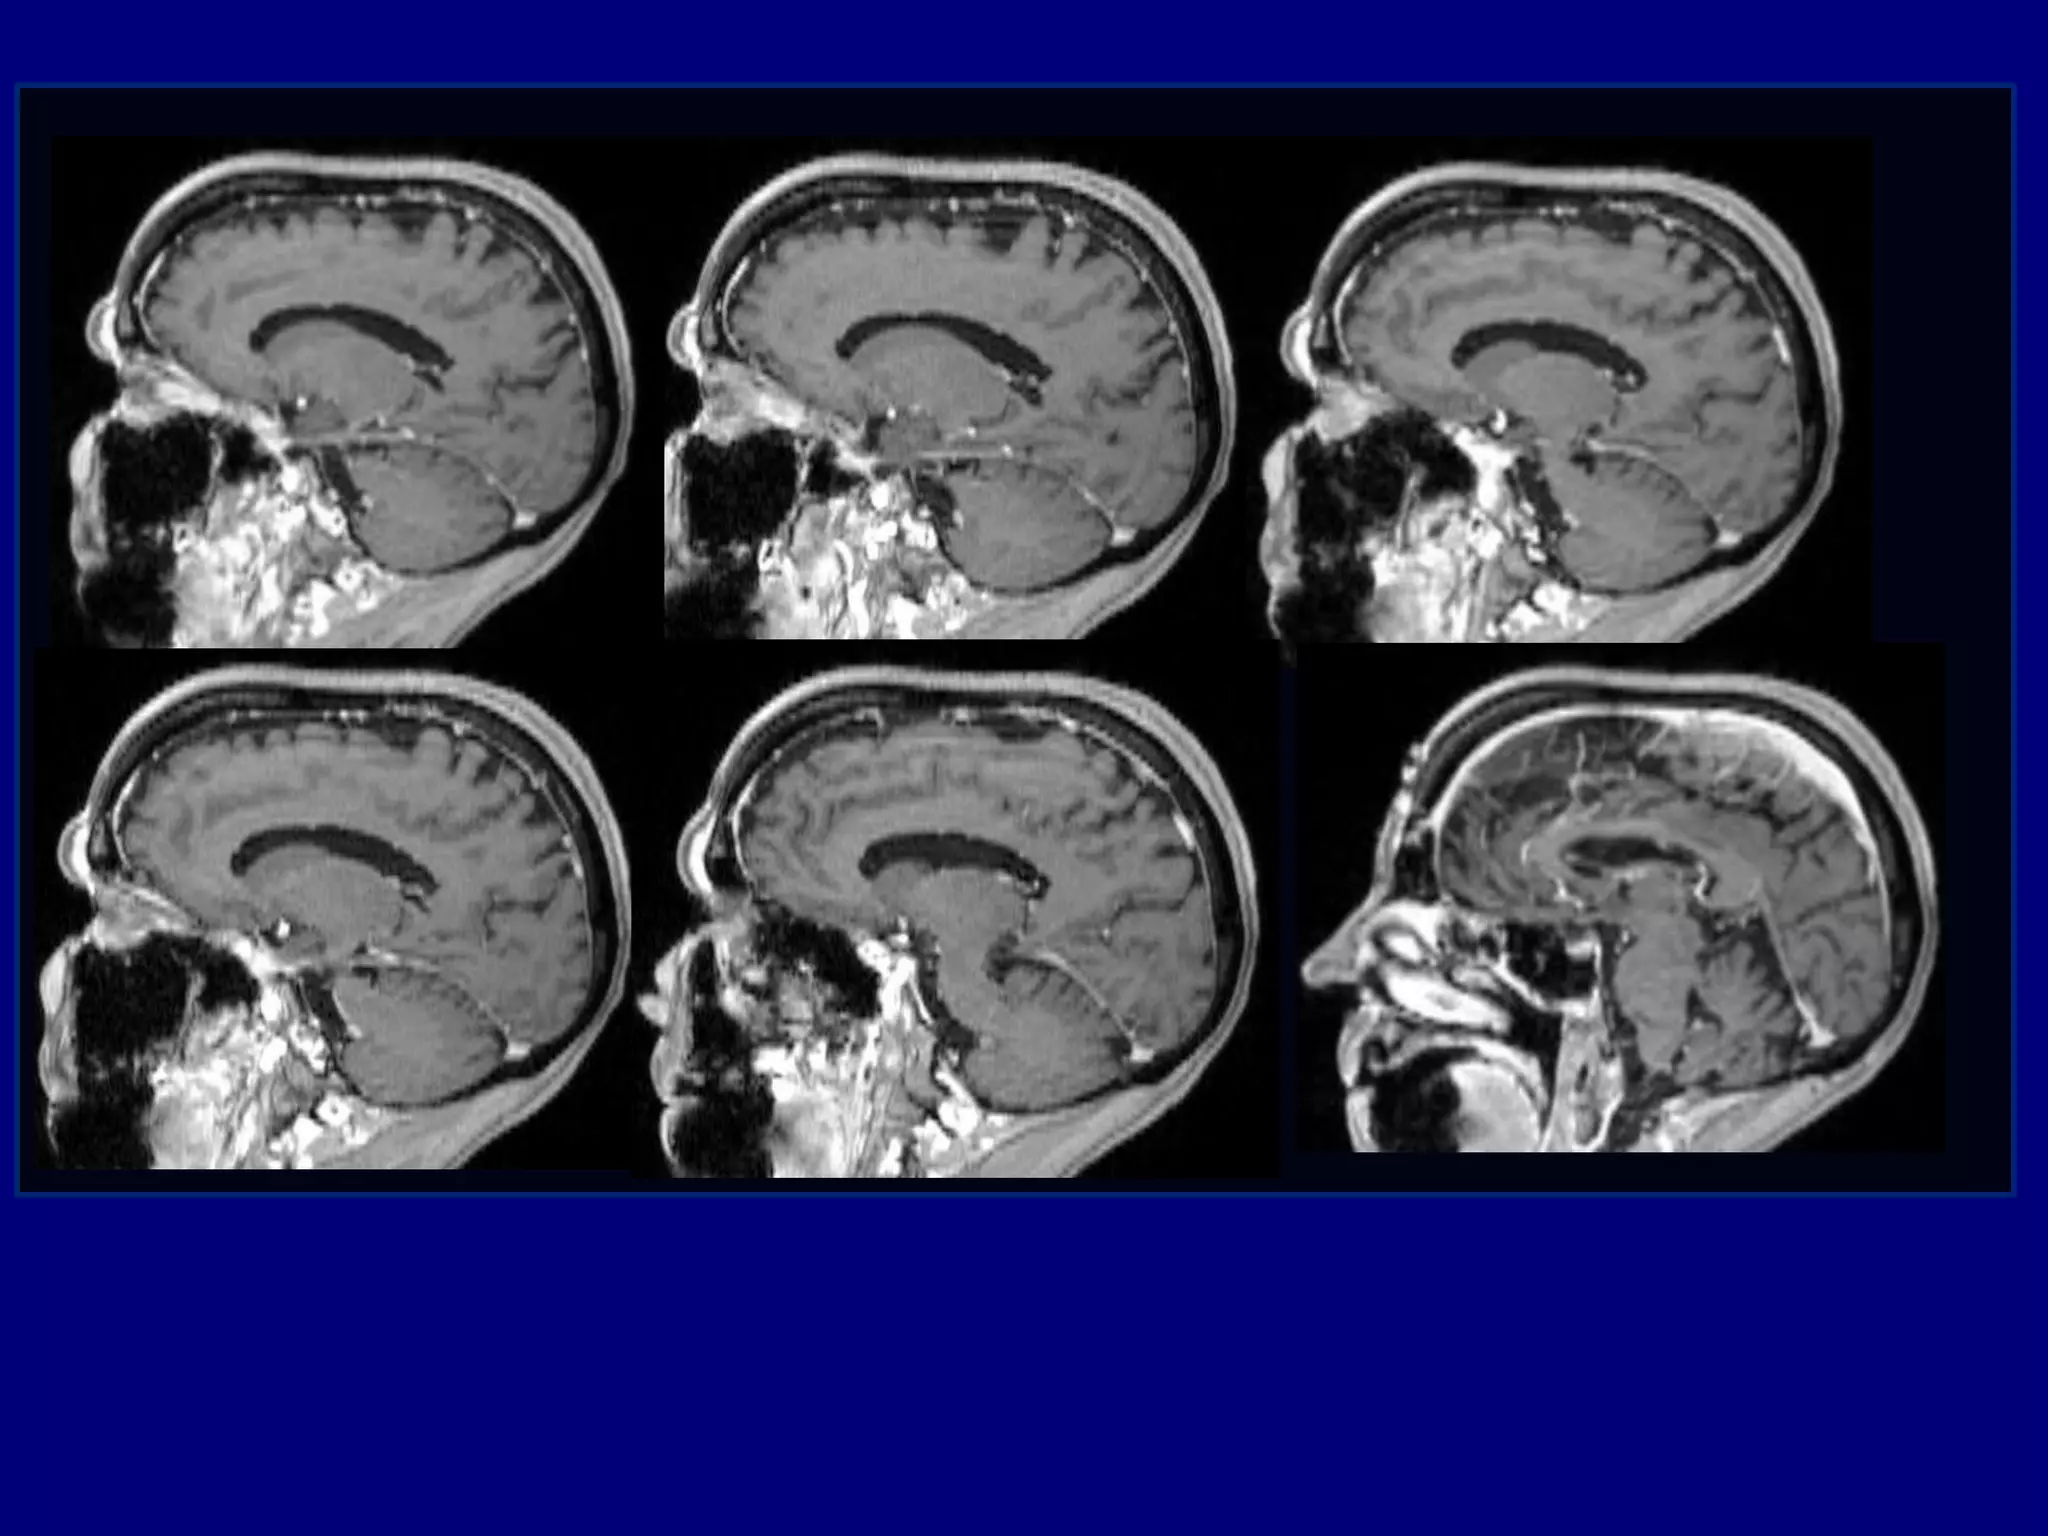

59-year-old male with the history of a slow

growing bony tumor of his right calvarium

The mass has grown over several years

No similar masses elsewhere

No associated neurological symptoms or pain

Medical consultation for cosmetic reasons

Computed Tomography

Magnetic Resonance Imaging

Post-gadolinium MPRAGE images for surgical planning